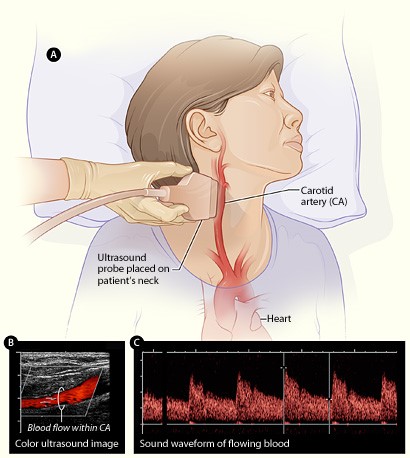

- Ultrasound and Color Doppler-Guided Surgery The purpose of the study is to examine the opinions of the trainees attending a training course concerning the use of technology.

Ultrasonography is an imaging technique that uses the reflections of high-frequency sound waves to create an image of a structure located within the body.